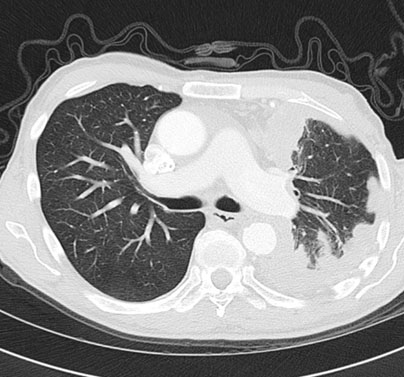

Tomografía computarizada (TC) de tórax: La TC de tórax es una técnica de imagen más precisa que puede mostrar con mayor detalle las alteraciones pleurales, como engrosamiento, calcificaciones, masas o derrame pleural (Figuras 4, 5 y 6).

El mesotelioma pleural es un tipo de cáncer que afecta el revestimiento delgado que rodea los pulmones y la cavidad torácica, conocido como mesotelio. El diagnóstico diferencial del mesotelioma pleural implica distinguirlo de otras enfermedades que pueden presentar síntomas similares (Figuras 7 y 8). Algunas de las condiciones que deben considerarse en el proceso de diagnóstico diferencial incluyen:

Pruebas de imagen: Se utilizan diversas pruebas de imagen para evaluar la presencia de anormalidades en la cavidad pleural. Estas pueden incluir radiografías de tórax con técnica OIT, tomografía computarizada (TC) de tórax, resonancia magnética (RM) y ecografía de tórax. Estas pruebas ayudan a detectar la presencia de derrame pleural, engrosamiento pleural, masas o nódulos en la pleura.